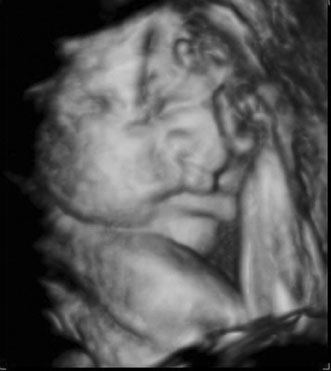

First trimester ultrasound may be performed transabdominally or transvaginally. Table 7 lists the components of a first trimester ultrasound. A crown–rump length, done between 7 and 13 weeks, can define a gestational age to within 5 days (Fig. 7).

Fig. 7. First trimester ultrasound showing crown–rump length.